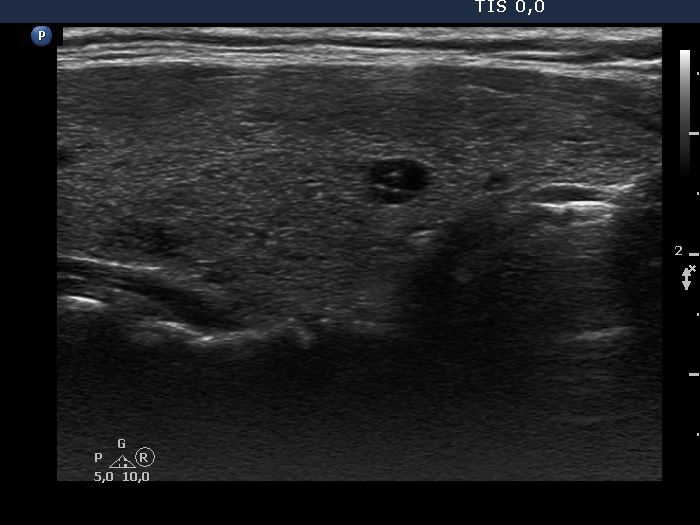

Consecutive patients with the final diagnosis of Hashimoto's thyroiditis - case 52 (1172) (ultrasonographic picture 3)

Lower part of the right lobe, longitudinal view.